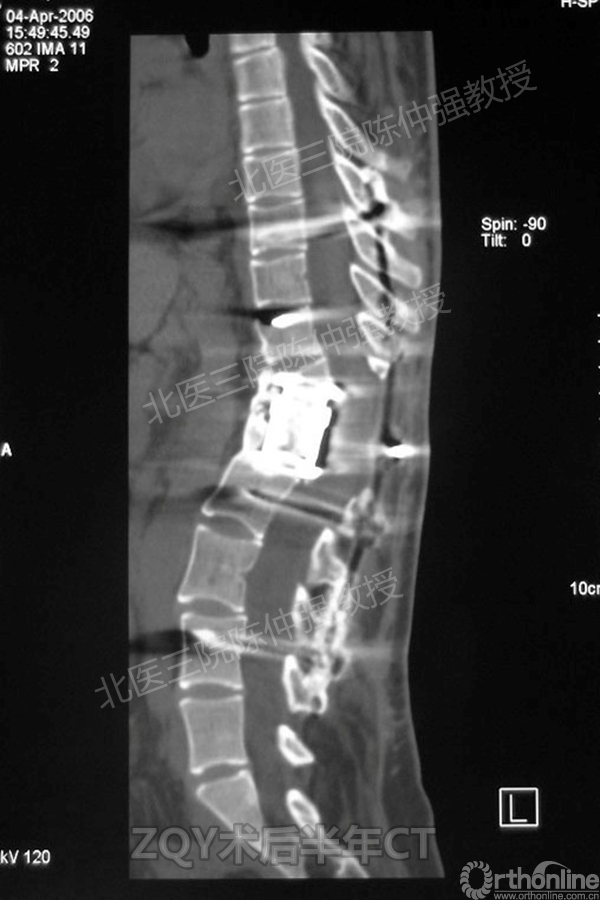

ZQY术后半年

患者女性17岁,胸腰椎陈旧结核性侧后凸畸形,局部呈“麻花状”扭转,无神经功能受损表现。2005年,陈仲强教授带领团队实施后路+侧前方联合入路脊柱节段切除、双轴旋转矫形术。术后患者外观显著改善,神经功能正常。术后随访证实患者截骨矫形节段骨性融合良好,矫形效果持续良好。